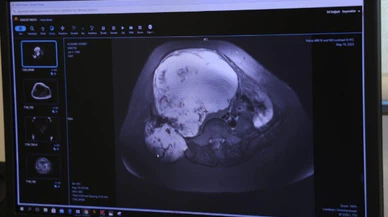

Ameliyat Haberleri

Son Dakika Ameliyat Haberleri

Bu sayfada güncel gelişmeleri takip edenler için Ameliyat ile ilgili en son gelişmeler ve son dakika Ameliyat haberleri sunulmaktadır. Ameliyat videoları, Ameliyat fotoğrafları ve Ameliyat haberleri